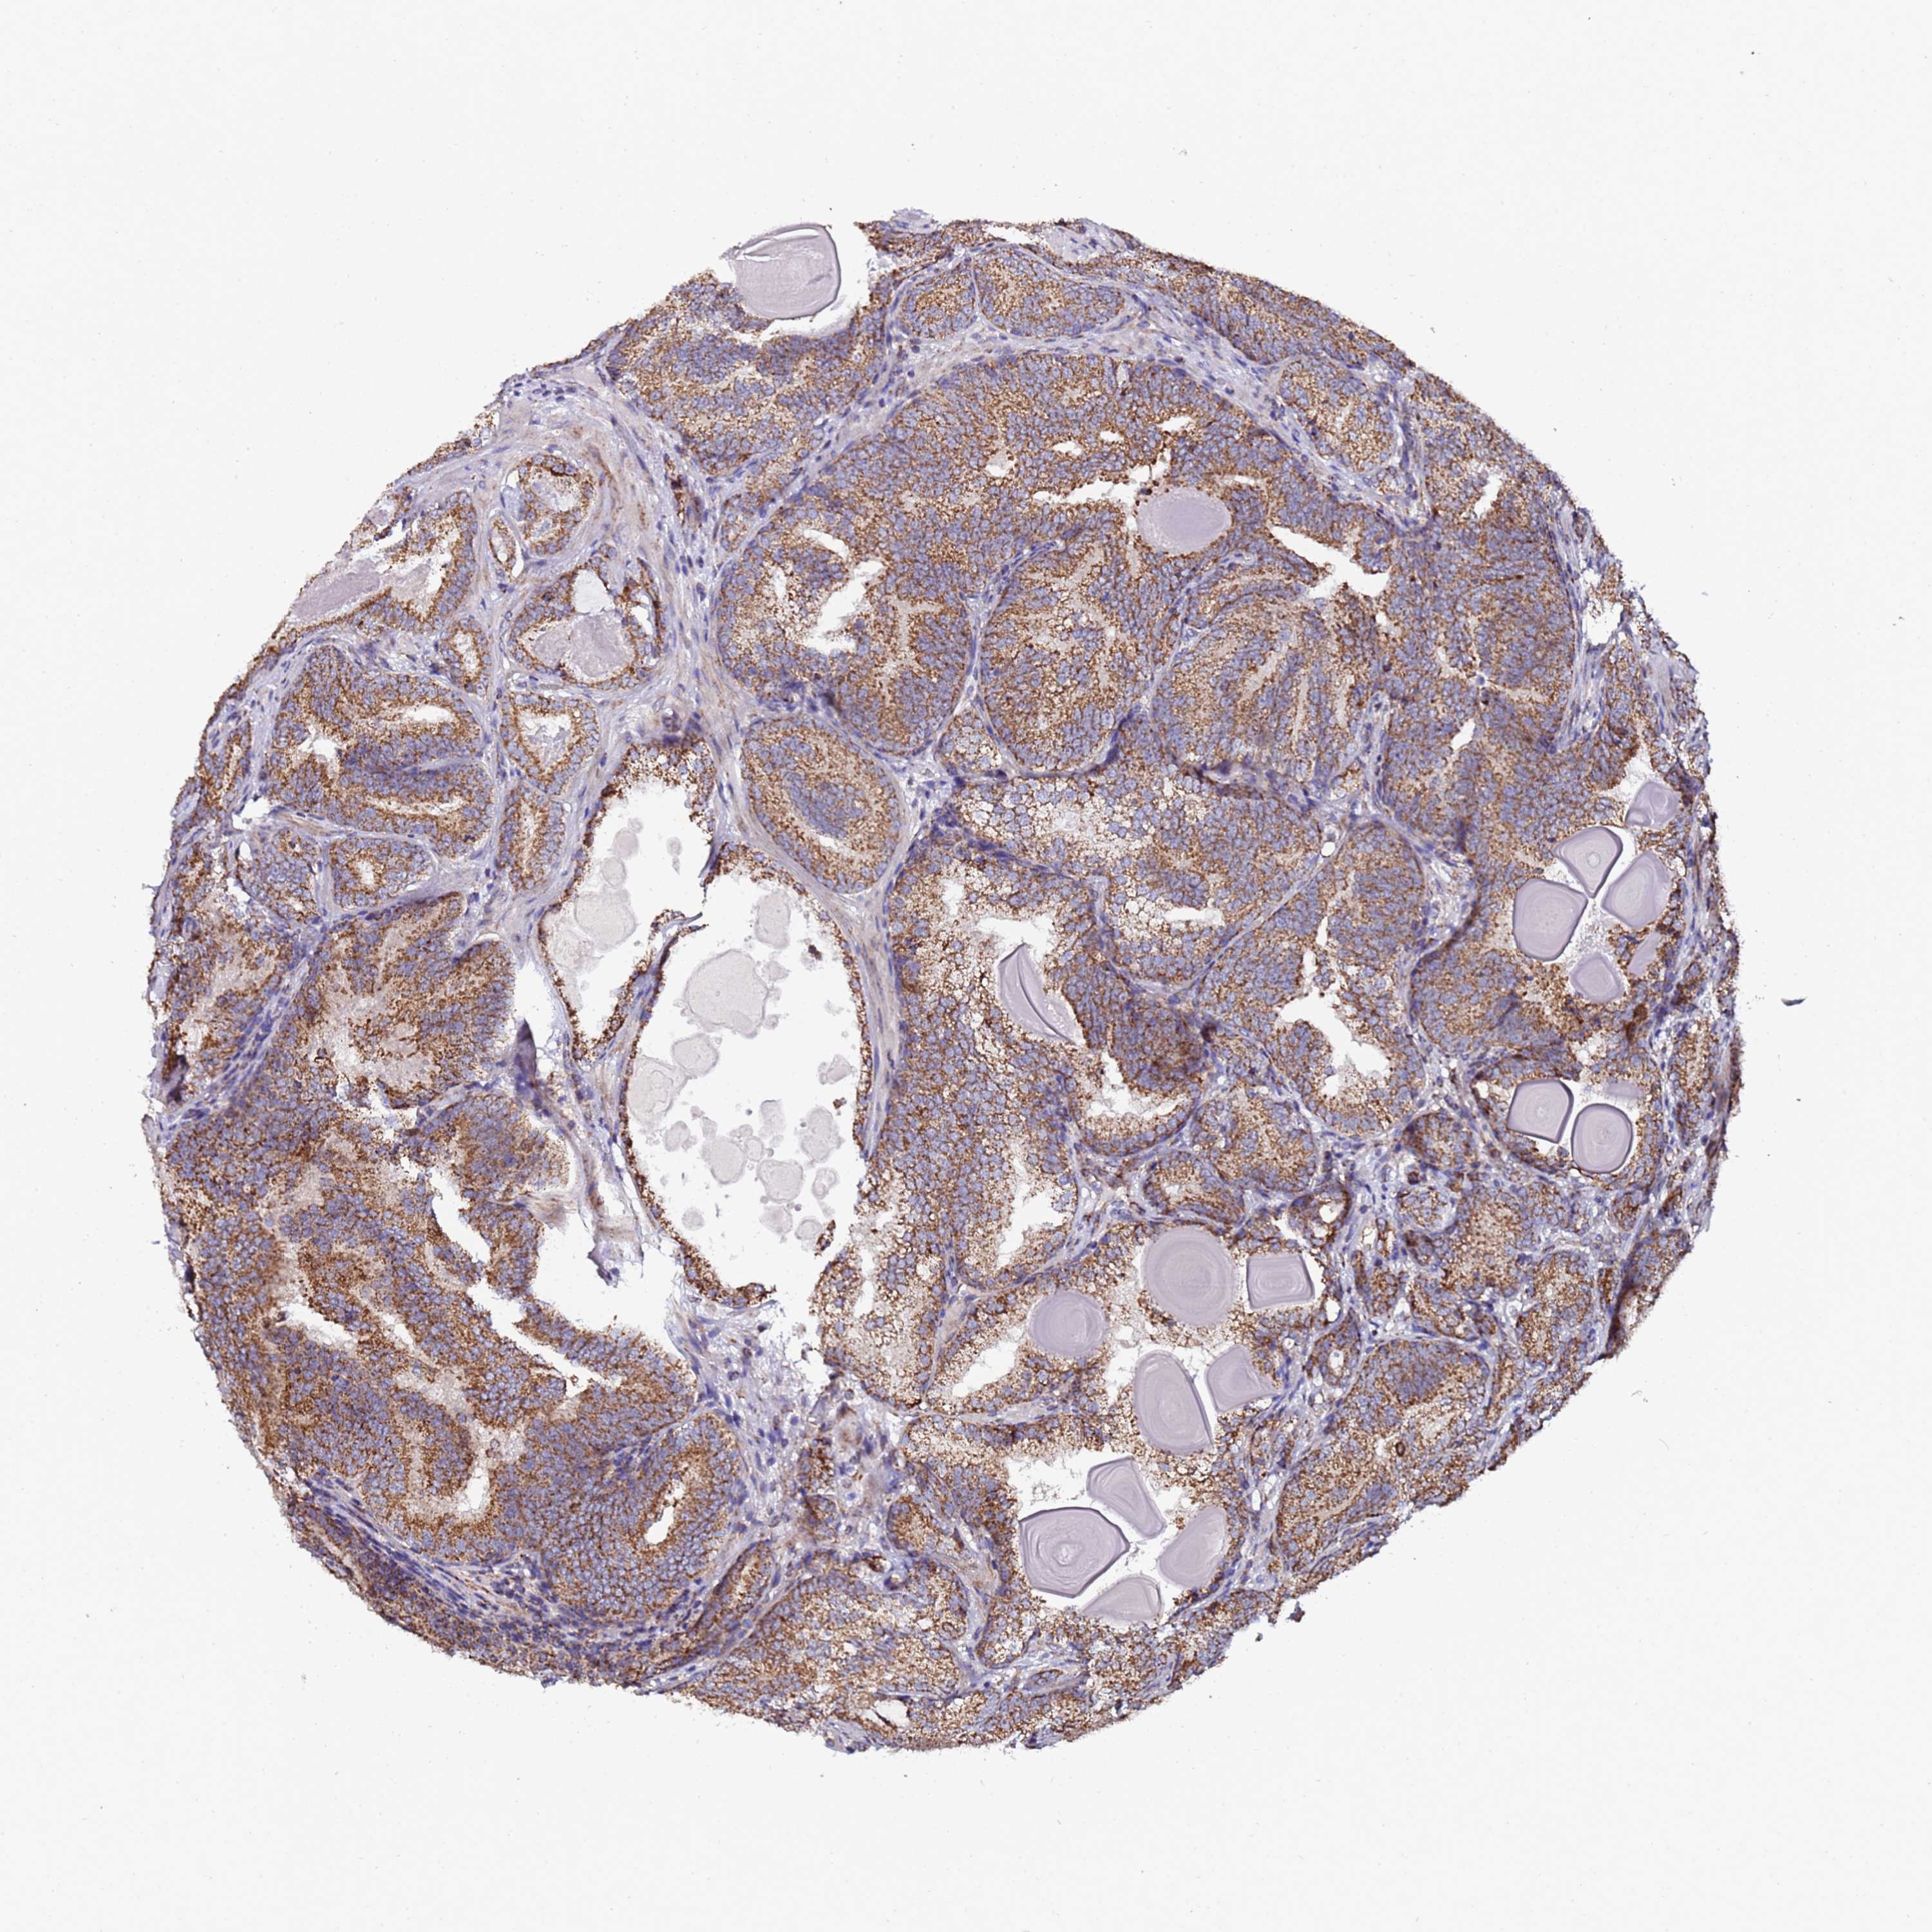

PROSTATE CANCER - Protein expressioni

A mouse-over function shows sample information and annotation data. Click on an image to view it in a full screen mode. Samples can be filtered based on level of antibody staining by selecting one or several of the following categories: high, medium, low and not detected. The assay and annotation is described here.

Antibody stainingi

Antibody staining in the annotated cell types in the current human tissue is reported as not detected, low, medium, or high, based on conventional immunohistochemistry profiling in selected tissues. This score is based on the combination of the staining intensity and fraction of stained cells.

Each image is clickable and will lead to virtual microscopy that enables deeper exploration of all samples and also displays staining intensity scores, fraction scores and subcellular localization as well as patient and tissue information for each sample.

Antibody HPA046775

Antibody HPA050633

Staining

High

Medium

Low

Not detected

Intensity

Strong

Moderate

Weak

Negative

Quantity

>75%

75%-25%

<25%

None

Location

Nuclear

Cytoplasmic/membranous

Cytoplasmic/membranous,nuclear

Adenocarcinoma, NOS

Adenocarcinoma, High grade

Adenocarcinoma, Low grade